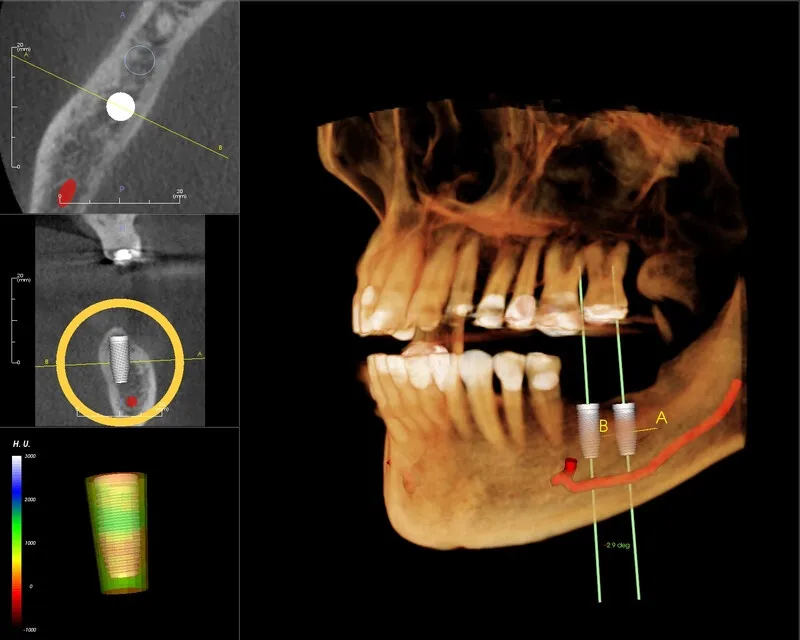

Trước khi trả lời câu hỏi chụp CT Conebeam ở đâu Hải Phòng, hãy cùng tìm hiểu tổng quan về phương pháp nha khoa này. Chụp CT Conebeam (Cone Beam Computed Tomography – CBCT) là một công nghệ hình ảnh tiên tiến sử dụng tia X để tạo ra hình ảnh 3D cực kỳ chi tiết của các cấu trúc trong vùng hàm mặt. Trong đó bao gồm răng, xương hàm, mô mềm và ống thần kinh. Khác với các phương pháp chụp X-quang truyền thống chỉ cho phép quan sát hình ảnh 2D phẳng, CT Conebeam cung cấp một “bản đồ” 3D toàn diện, cho phép nha sĩ nhìn thấy các mô và cấu trúc xung quanh từ nhiều góc độ khác nhau. Điều này giúp cải thiện độ chính xác trong việc chẩn đoán và lập kế hoạch điều trị.

Hệ thống Conebeam kết nối máy tính và phần mềm chuyên dụng để xử lý dữ liệu, tạo ra các hình ảnh sắc nét và dễ dàng phân tích. Với khả năng cung cấp thông tin chi tiết về xương hàm và mô mềm, phương pháp này là công cụ hỗ trợ đắc lực trong nhiều lĩnh vực nha khoa, từ cấy ghép implant, chỉnh nha, cho đến phẫu thuật hàm mặt. Bằng cách này, các bác sĩ có thể đưa ra những quyết định điều trị chính xác và an toàn hơn, giảm thiểu rủi ro và nâng cao hiệu quả điều trị.

- Cấy ghép Implant: Một trong những ưu điểm lớn của CT Conebeam là khả năng đánh giá mật độ xương tại khu vực cấy ghép. Bằng cách sử dụng hình ảnh 3D, bác sĩ có thể quyết định liệu có cần ghép xương hay không và chọn đường kính implant phù hợp nhất với ổ xương. Nếu không sử dụng CT Conebeam, bác sĩ có thể chỉ chọn implant có đường kính nhỏ nhất để đảm bảo an toàn. Tuy nhiên, điều này có thể không tối ưu cho tuổi thọ lâu dài của implant.